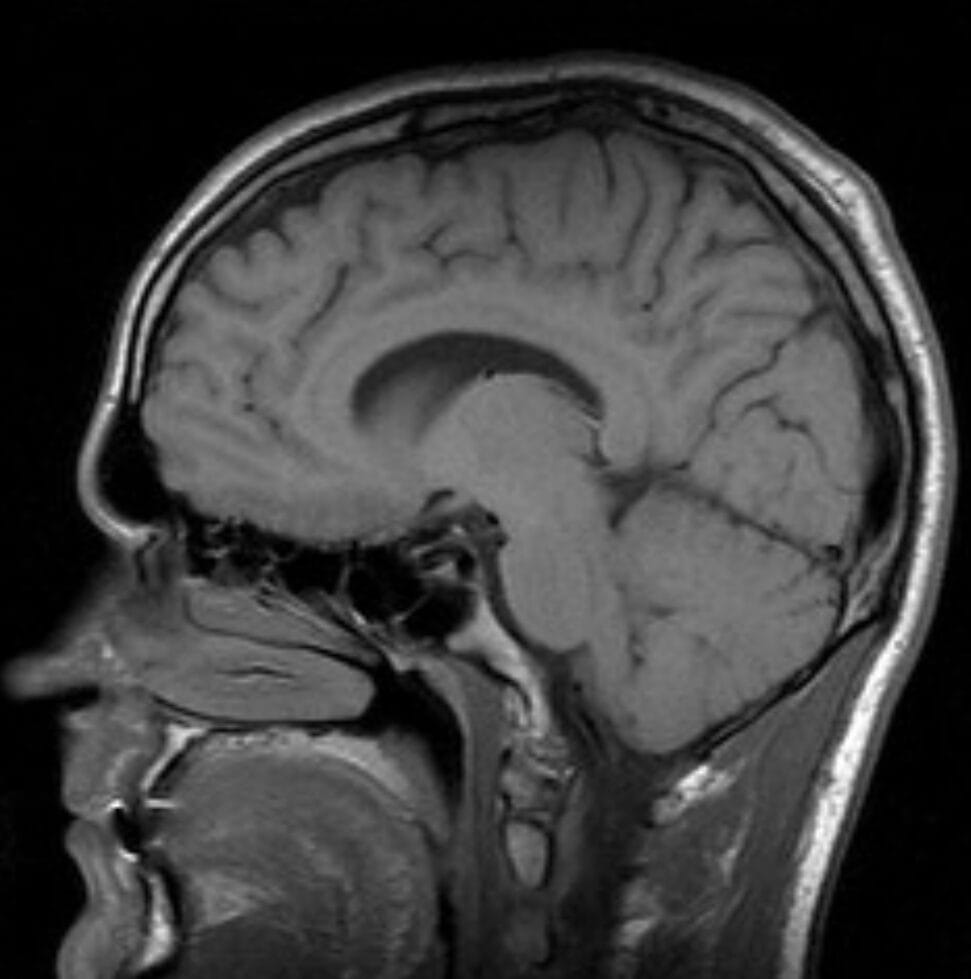

“Brain” by alaspoorwho is licensed under CC BY-SA 2.0.

Additional research from Princeton University’s Music Cognition Lab examines what happens in the brain when experiencing music and suggests that the sound activates certain parts of the brain, including motor and sensory areas, which affect emotions, imagination, and daydreaming, and that this is a powerful tool for promoting brain health.